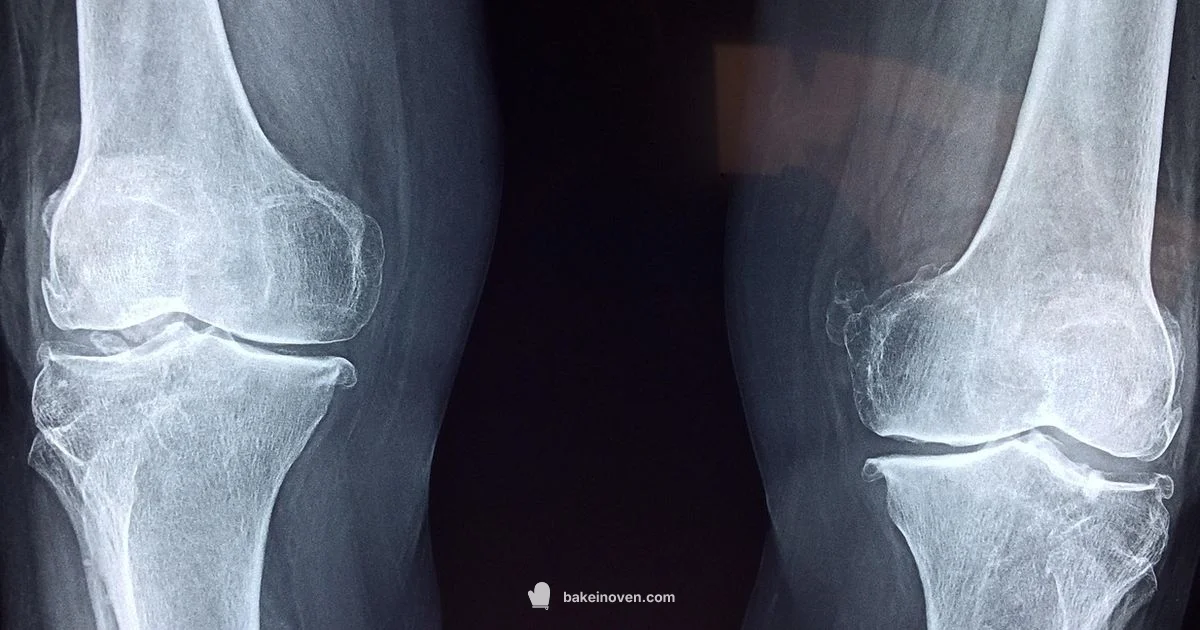

Diagnosis starts with a physical exam, focusing on the knee and the area behind it. Your clinician may palpate the swelling and assess range of motion, joint stability, and gait. Imaging tests help confirm the presence of a cyst and identify underlying issues. An ultrasound is commonly used because it can visualize fluid-filled structures and guide aspiration if needed. An MRI provides a more detailed view of soft tissues, helping to distinguish a cyst from other behind-the-knee masses and revealing underlying meniscal tears or cartilage damage. X-rays are useful to assess associated osteoarthritis and bone alignment, even though they don’t show the cyst itself. A comprehensive assessment is key to tailoring treatment.